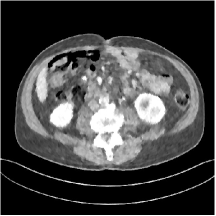

First, we study transform training based on Mayo Clinic data. As shown in Fig. 6, seven slices obtained at regular dose from three patients are used for transform learning. The number of pixels . Similar to the phantom experiments, overlapping patches are extracted with a patch stride. The number of overall training patches is about . We set for ST, , , for MARS2, , , , , for MARS3, , , , , , , , , for MARS5, , , , , , , , , , , , , for MARS7. The iteration number in Algorithm 1. Fig. 7 illustrates the learned transforms obtained with Mayo Clinic data. Different from the XCAT phantom case, these transforms up to MARS5 display more complex features and structures. The rich features of the MARS models better sparsify the training images over layers compared to the single-layer model (ST).

Figs. 8, 9, 10, and 11 show the reconstructions of the four independent slices using the FBP, PWLS-EP, PWLS-ST, PWLS-MARS2, PWLS-MARS3, PWLS-MARS5, and PWLS-MARS7 schemes, respectively. Additional Mayo Clinic experimental results of the parameter tuning case (Fig. 15) are shown in the supplementary document. Table 1 lists the RMSE and SSIM values of reconstructions of the four independent test slices, with the best values bolded. Generally, the five and seven layer models provided the best RMSE and SSIM values. They outperform the single-layer model by HU in RMSE on average. However, the MARS5 and MARS7 models perform similarly. In order to strengthen the benefits of the multi-layer model, Table 2 lists the RMSE of the reconstructions in four different ROIs (shown in the reference of Fig. 11) with seven methods for slice 100 of patient L506. By observing the reconstructed images, we see that although the ST model achieves a cleaner reconstruction result than FBP and PWLS-EP, it still sacrifices some sharpness of the central region and suffers from loss of details. The deeper models have a somewhat more positive effect in terms of maintaining subtle features, which is clearly more essential to clinical diagnosis. Furthermore, as we will discuss later, after considerable parameter tuning, we found that the information contained in residual maps is gradually decreased with the number of layers, eventually vanishing at some layer, which suggests that very deep unsupervised models might not offer significantly better image quality.

We trained models from patches of (regular-dose) slices of the XCAT phantom and Mayo Clinic data and tested the models for reconstructing other slices. The learned multi-layer models contain complex features and structures, which help enhance image reconstruction quality of MARS models over single layer models. Experiments with both simulated data from the XCAT phantom and with the synthesized clinical data reveal that PWLS-MARS provides better reconstruction metrics and image details compared to other methods such as FBP, PWLS-EP, and PWLS-ST. In Figs. 8, 9, 10, and 11, we observed that the reconstruction incorporating deep transform model prior presented more subtle details, especially for the central region, which normally suffers from severe artifacts in low-dose CT reconstruction.